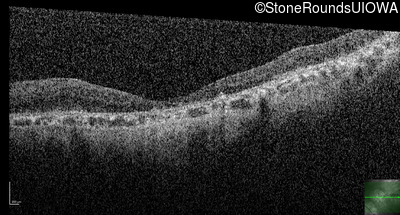

Optical Coherence Tomography - Right - 1/200 sc

Exemplar / OCT Stack